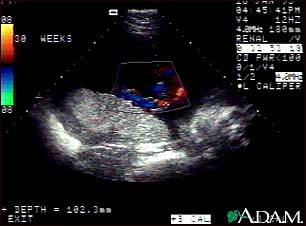

Ultrasound, color - normal umbilical cord

This is a normal color Doppler ultrasound of the umbilical cord performed at 30 weeks gestation. The cord is the colored area in the middle of the screen, with the different blood vessels represented by different colors. There are normally three vessels in the cord, two arteries and one vein. The umbilical cord is connected to the placenta, located in the middle left of the image.